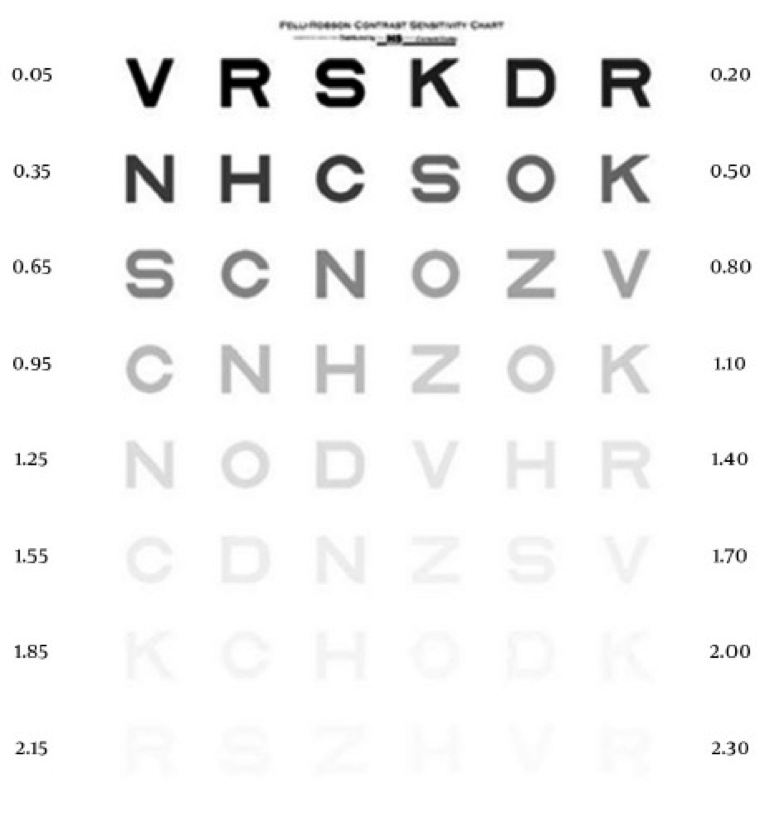

Examen de sensibilidad al contraste

El examen de sensibilidad al contraste utiliza la tabla de sensibilidad al contraste de Pelli-Robson. Esta tabla utiliza letras del mismo tamaño que progresan de alto a bajo contraste.18 Cuanto más difícil sea para una persona distinguir las letras, menor será su sensibilidad al contraste. En la DMAE, los exámenes de sensibilidad al contraste ayudan a detectar anomalías visuales que podrían no ser captadas en un examen de agudeza visual.19